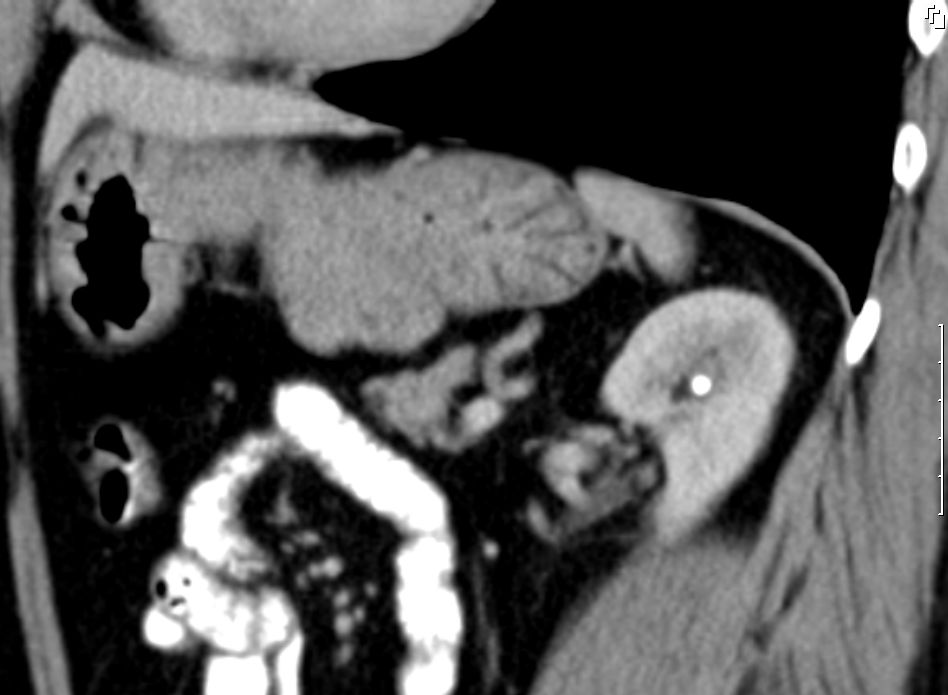

84-jährige Frau mit symptomatischer Anämie (Hb 3,8) und Kachexie (BMI 16).

Palpable Resistenz im Epigastrium.

Intraoperativ fand sich im Mesenterium des Jejunum eine 4cm große knotige Raumforderung.

Histologisch gastrointestinaler Stromatumor. Exzision im Gesunden. Ki67 = 1 % (niedriges Risiko).![]() |